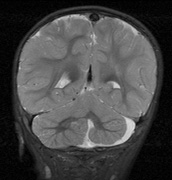

Intracranial leptomeningeal capillary vascular malformation (Figs. 21 and 22) is associated with seizures and contralateral neuromuscular weakness. Central nervous system involvement correlates highly with ipsilateral involvement of the V1 dermatome by a PWS.208,218

Fig. 22. Axial T2-weighted (a) and coronal T1-weighted (b) images of a 16-year-old boy with a port-wine lesion over the right side of his face. The right hemisphere is markedly atrophic and abnormal draining veins are seen within the right lateral ventricle (arrowheads). (c, d) The entire right hemisphere is covered by an enhancing pial angioma and the choroid plexi are enlarged. Enhancing retinal angiomas (arrows), typical of Sturge-Weber syndrome, are seen in (d).